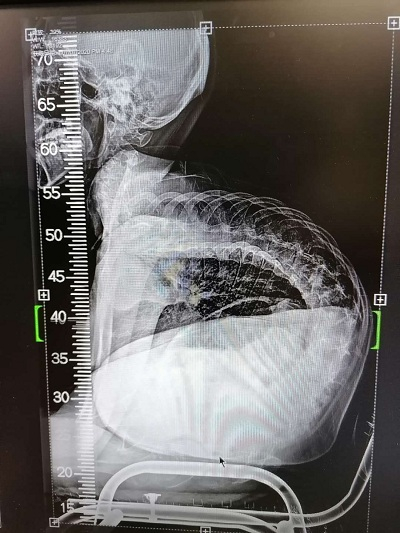

跑、跳这些最平常的动作,对于17岁的浙江大男孩小徐来说却是幻想,有时就连吃饭和呼吸都是一种奢侈。因患有罕见病脊髓性肌萎缩症,小徐脊椎严重弯曲,肌肉萎缩无力,大部分时间都只能躺在床上。即便如此,小徐一直没有放弃治疗,热爱生命的他用坚强的意志打动了很多人。

近日,小徐在上海交通大学医学院附属新华医院脊柱中心接受了脊柱矫形手术,穿上了“螺钉护甲”,身体外观和生命质量都大为改观,被疾病严重扭曲的身体一夜变直。小徐说,“命运对我虽然残酷,但我不会放弃任何希望,坚强生活。如果有余力的话,我还想帮助更多的人!”

长到17岁的小徐,身形弯曲,大部分时间都只能像蛇一样匍匐躺在床上,还常常呼吸困难,轻微的肺部感染就有发生呼吸衰竭的可能,甚至有生命危险。即便如此坎坷,但小徐始终不放弃求生的信念。

小徐因为神经肌肉萎缩,极重度侧弯,如果进行手术,术后极其容易出现呼吸衰竭。面对如此大风险的高难度手术,小徐的心肺功能是否能够耐受?术后会不会呼吸机拔管失败?

7月8日当天,新华医院杨军林教授的团队仅用了5个小时就完成了这样一例极重度的脊柱矫形手术,术中输血很少,一枚一枚的螺钉置入了身体中,犹如一件“螺钉护甲”,将小徐的脊椎托了起来,小徐蛇形的身体变直了。术后,小徐进入了监护室进行观察,各项生命体征都很平稳,当晚就拔除了气管插管进行自主呼吸了。专家透露,如果小徐恢复顺利,他身体外观和生命质量都将大为改观。